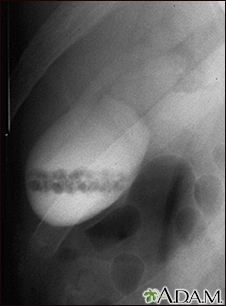

Gallstones, cholangiogram